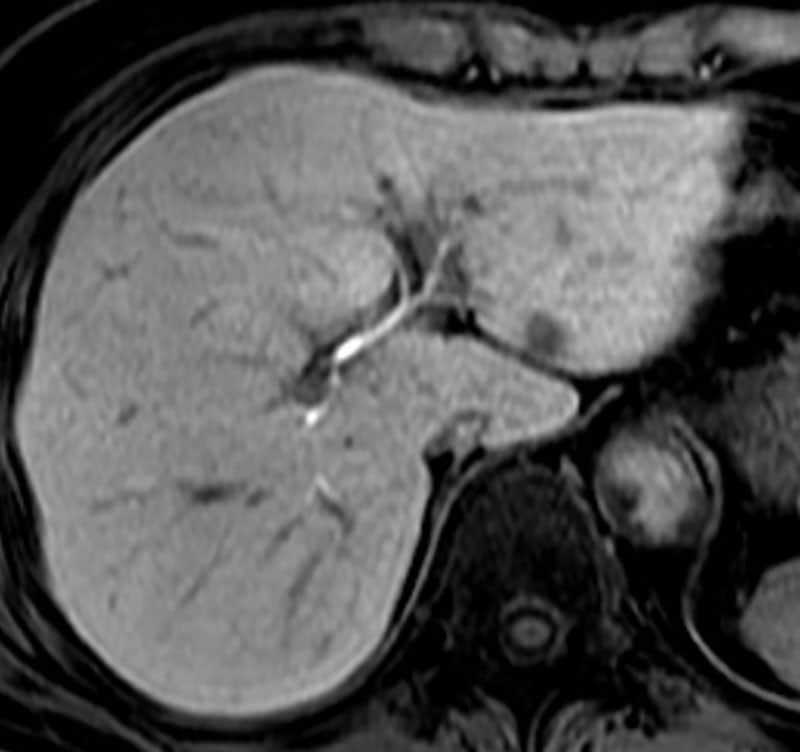

図1.単純脂肪抑制T2WI

肝S2に8mm大の軽度T2WI高信号結節を認める。肝右葉に小さな血管腫疑いあり。